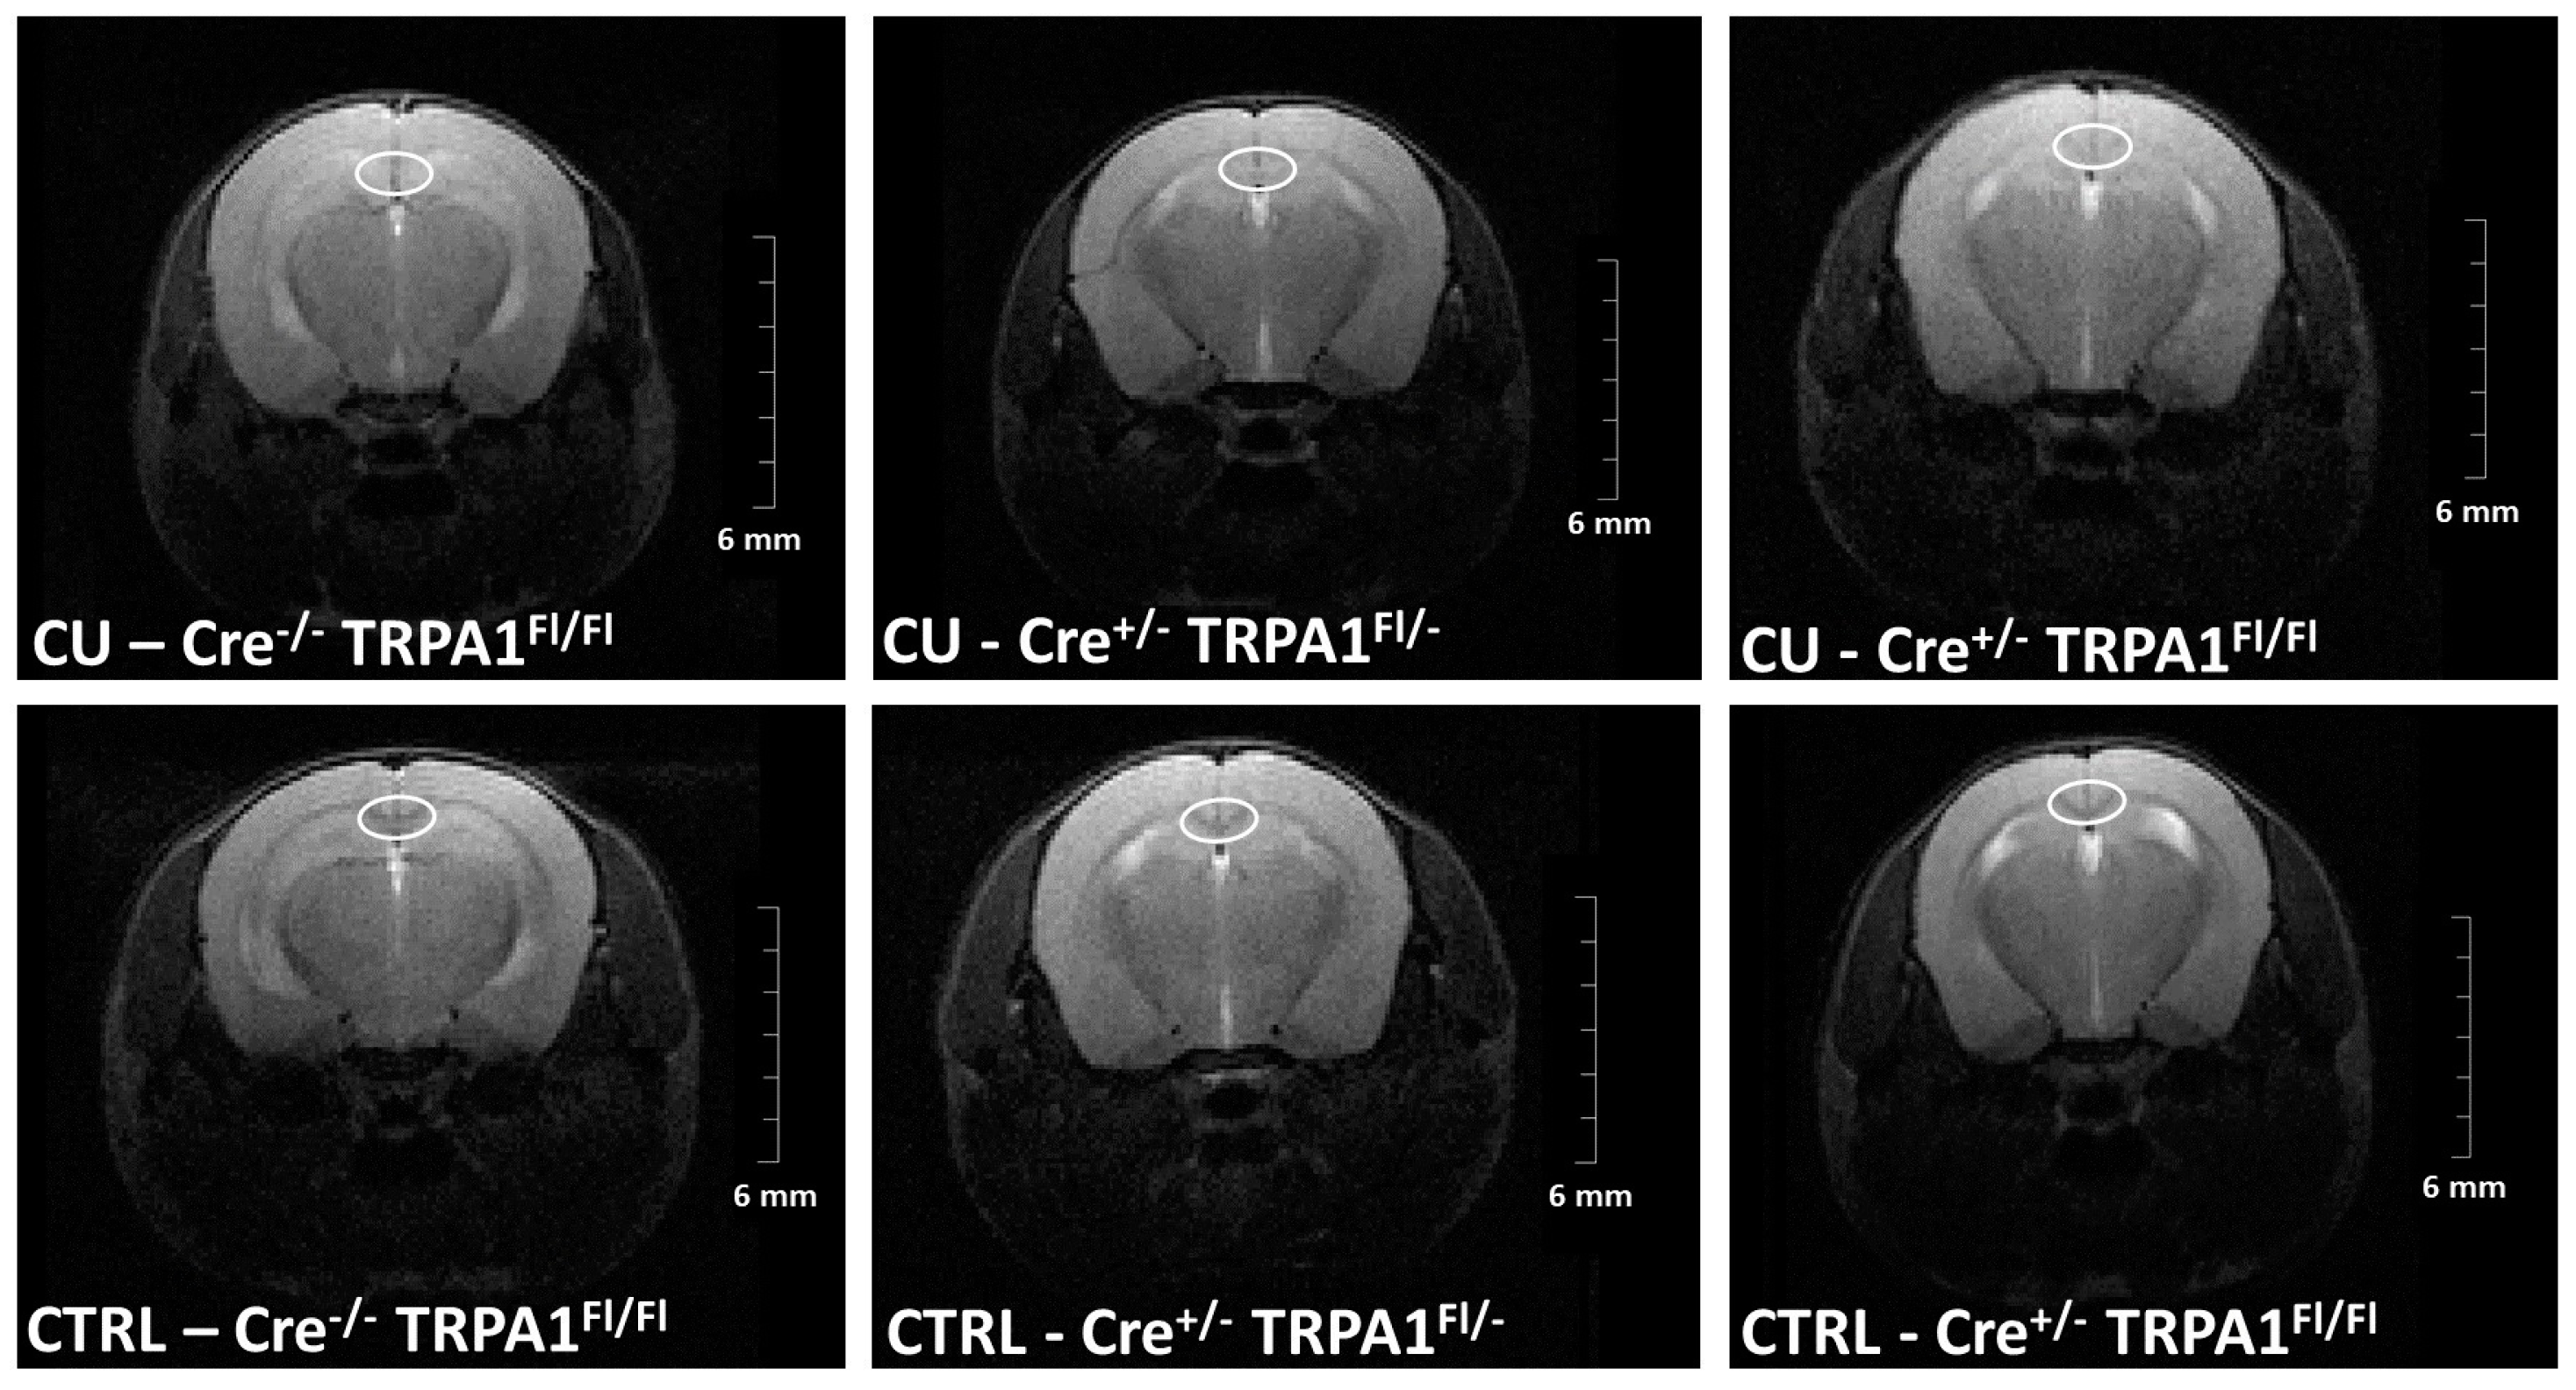

3.2. Magnetic Resonance Imaging (MRI)